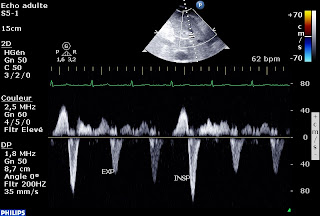

-Insuffisance tricuspide à « vélocité variable », véloce en expiration, avec un gradient VD-OD élevé traduisant une hypertension artérielle pulmonaire : en inspiration, l’IT devient massive, la vélocité devient faible,

et le reflux systolique dans les veines sus-hépatiques devient très net. Par ailleurs, la fonction systolique du VD est très abaissée.

Du fait de la grande variabilité respiratoire de la vélocité de l'IT et de l'inversion de la courbure septale, je dirais plutôt Péricardite constrictive.